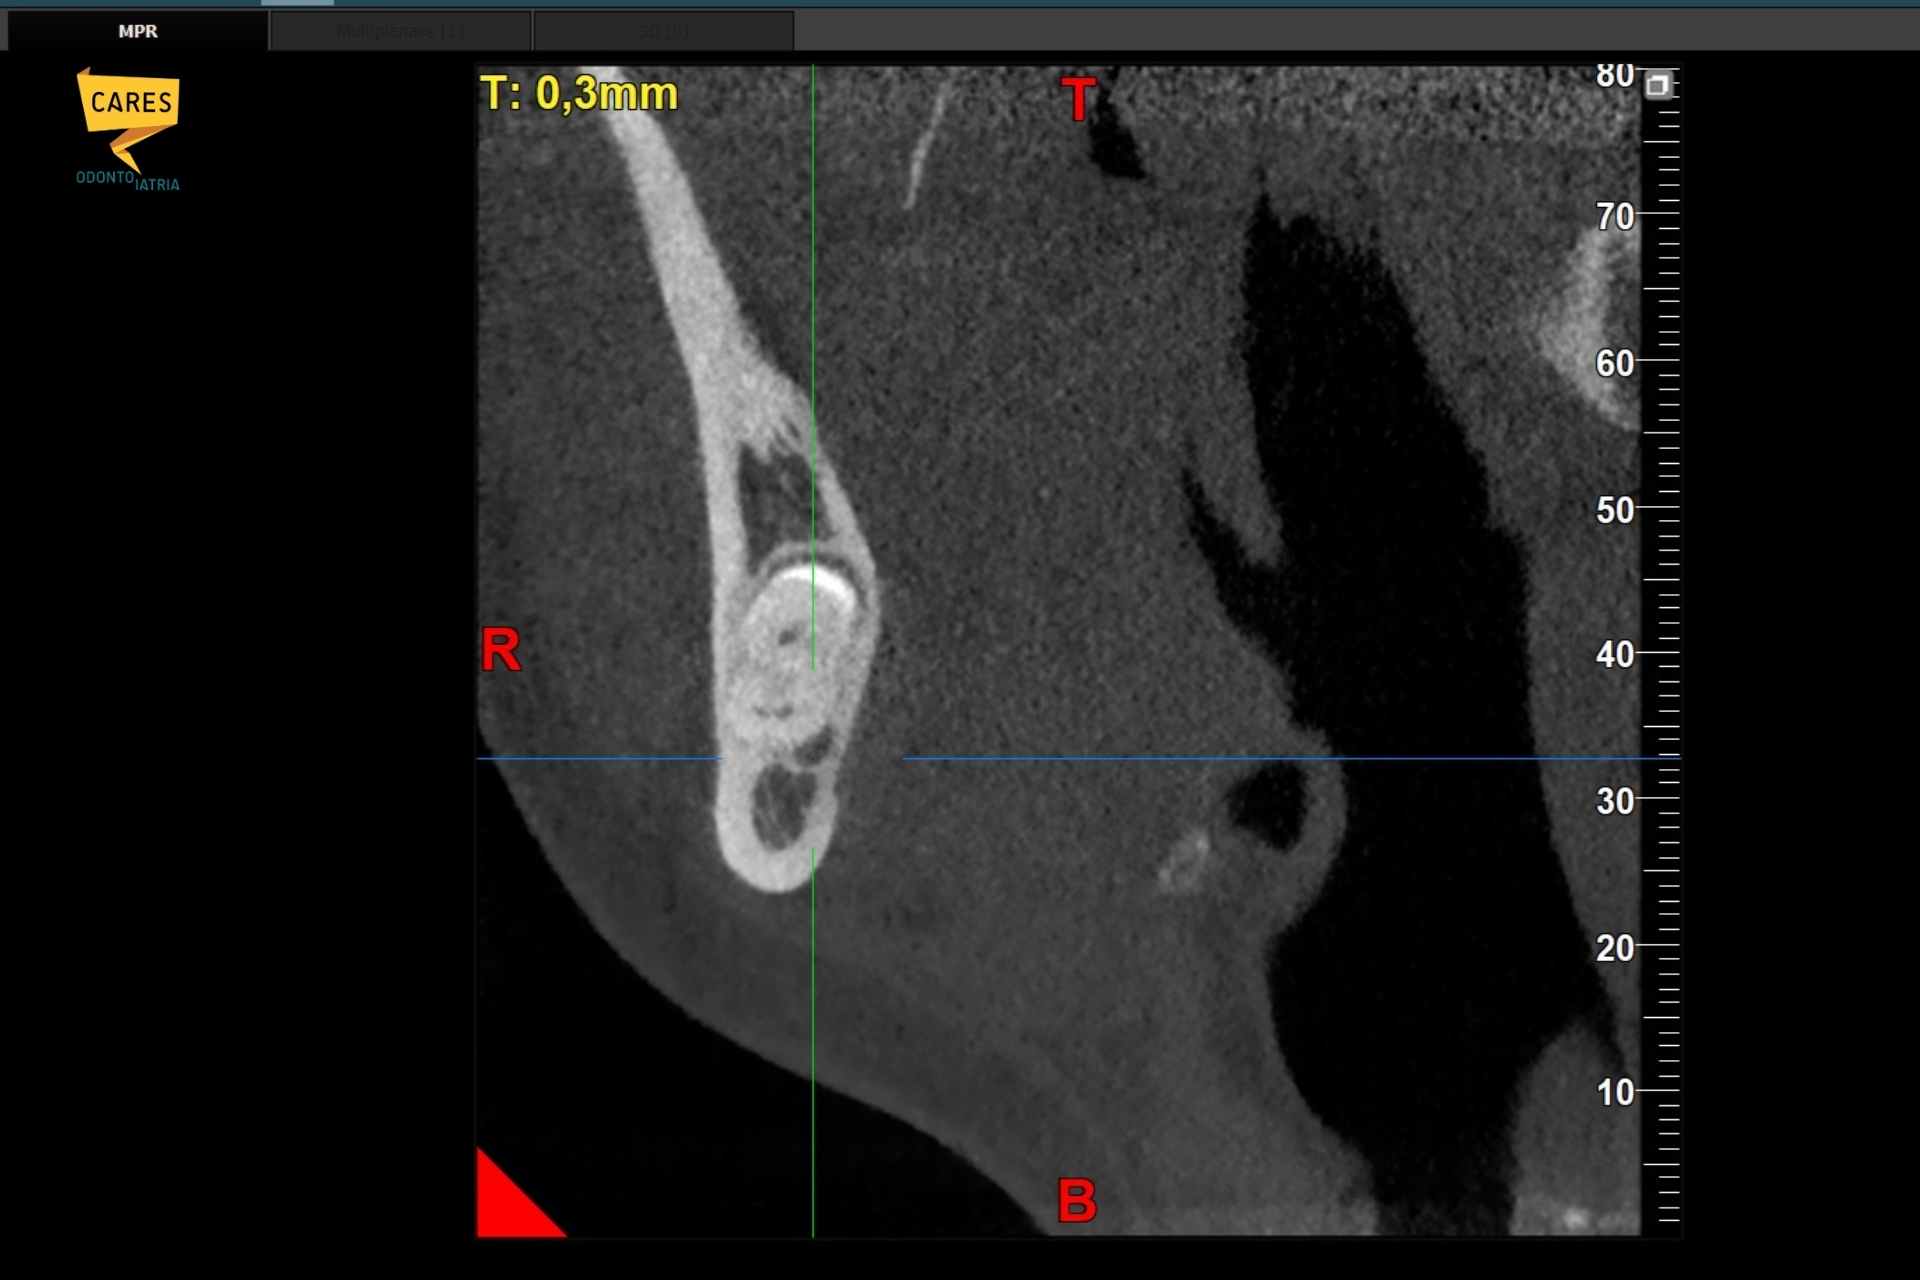

TAC 3D che mostra il dente del giudizio inferiore e la posizione del nervo alveolare prima dell’estrazione

La radiografia panoramica fornisce una visione generale, ma è bidimensionale. La TAC 3D, invece, permette di vedere esattamente:

• la posizione del dente del giudizio

• la forma e l’orientamento delle radici

• il rapporto preciso con il nervo alveolare

• lo spessore dell’osso

In pratica, consente al dentista di sapere prima dove intervenire e come farlo nel modo più sicuro possibile.

Grazie alla TAC tridimensionale possiamo capire, ad esempio, se il nervo si trova:

• sotto le radici

• tra le radici

• sul lato interno (linguale) del dente

Questa informazione cambia completamente l’approccio alla chirurgia. Sapere in anticipo dove si trova il nervo permette di pianificare un’estrazione del dente del giudizio mirata, riducendo il rischio di complicazioni e migliorando il post operatorio.